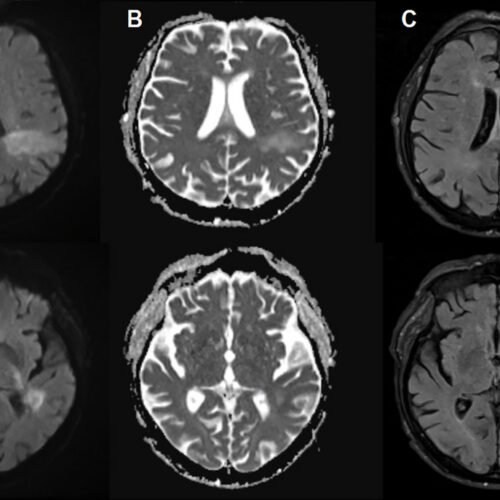

5. You're likely already infected with a brain-eating virus you've never heard of

You're likely already infected with a brain-eating virus you've never heard of

Open source article for the full coverage.

Ars Technica 3 hours ago